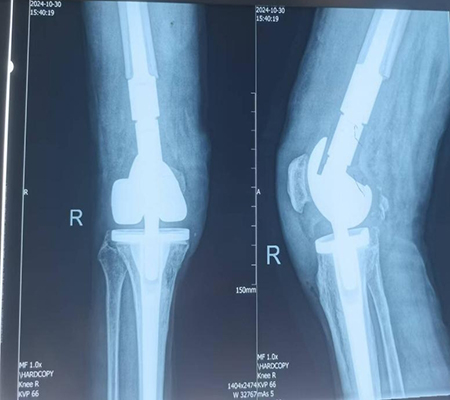

膝关节置换术后假体周围骨折,假体松动

手术由骨科专家许立新主任亲自主刀,在手麻科医护人员的全力配合下,顺利开展。手术过程中,发现膝关节假体彻底松动,胫骨假体也发生了松动,这再次证实了术前计划的合理性,去除松动假体后,安装特制肿瘤膝关节,手术过程非常顺利,仅用时86分钟。

膝关节置换术后假体周围骨折特殊假体返修术后